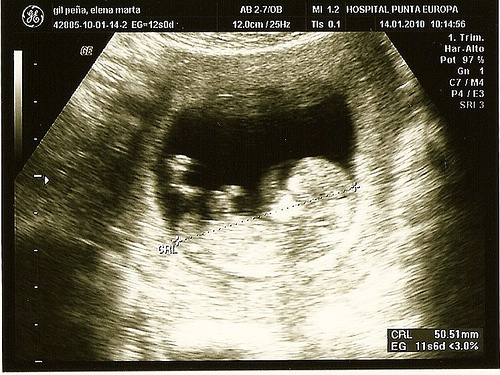

Ecografia ou Ultrassonografia:

É uma técnica bastante comum que serve tanto para detectar problemas como para obter a primeira imagem do seu bebê. Essa técnica ajuda a descobrir o sexo do neném e também permite o primeiro contato com possíveis anomalias, como defeitos no coração ou alterações cromossômicas.

A ecografia de segundo nível é um tipo de exame recomendado para observar mais de perto possíveis defeitos no feto. São indicados para quando os exames de detecção prévios já indicaram alguma anomalia.

Essa técnica não é invasiva e é aplicada por meio de um aparelho que cria uma imagem através de ondas sonoras. Permite a observação intrauterina sem causar qualquer incômodo ao bebê.